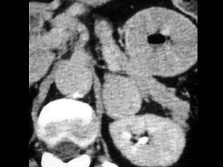

患者偶然发现肾上腺团块,结合所示图像,最可能的诊断是()

• A.转移

• B.脂肪瘤

• C.腺瘤

• D.嗜铬细胞瘤

• E.以上都不是